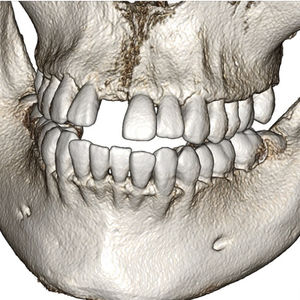

... Anatomage lleva más de diez años siendo líder del mercado en el desarrollo del software de renderizado 3D más avanzado para especialistas médicos y dentales. Invivo6, nuestra última versión, mantiene una interfaz de usuario intuitiva ...